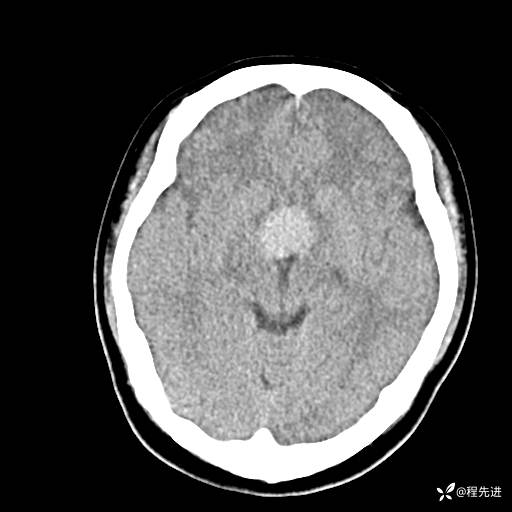

CT平扫: